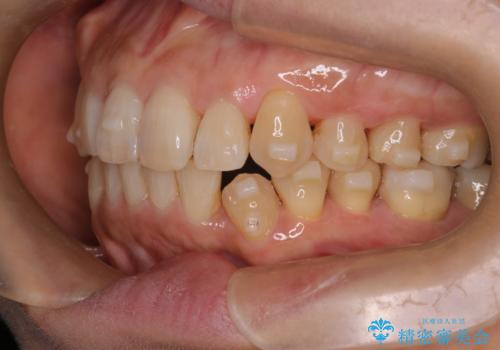

インビザラインで非抜歯矯正|ゴムかけで下顎犬歯の低位を改善し、噛み合わせも最適化

- 患者様は、下顎の犬歯が通常より低い位置にあり、噛み合わせのバランスが崩れていることを気にされて来院されました。診査の結果、抜歯せずに歯をきれいに並べるスペースを確保しながら、**ゴムかけ(顎間ゴム)**を使用して下顎犬歯の高さを適正に調整する方針を立てました。併せて、奥歯の噛み合わせも改善し、全体のバランスを整えることを目標としました。

治療はインビザライン(マウスピース矯正)を使用し、歯列全体を計画的に移動させながら、下顎犬歯の低位をゴムかけによって徐々に引き上げました。患者様にはゴムの装着をしっかり継続していただき、順調に改善が進行。最終的に奥歯の噛み合わせも安定し、全体の咬合バランスが整いました。治療後は「自然な噛み心地になり、見た目も満足」と患者様にも喜んでいただきました。